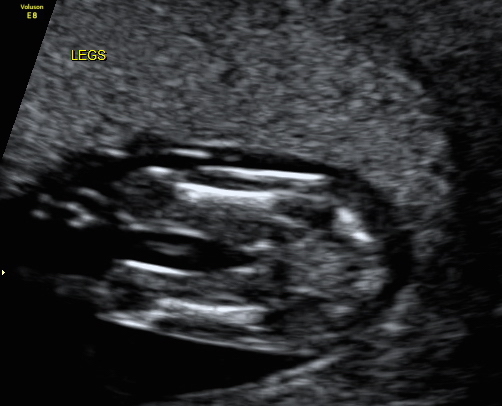

Hi, we have decided not to find out gender but i wanted to know what you ladies thought for a bit of fun while we wait! I'm not too sure if i can even see a nub in the profile but I thought someone here might be able too, also added the potty shot too, again i have no idea if you can see anything! Attachment 33070Attachment 33071